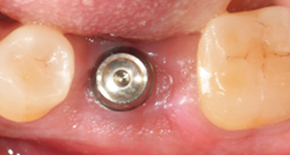

2. Suture after MagiCore placement